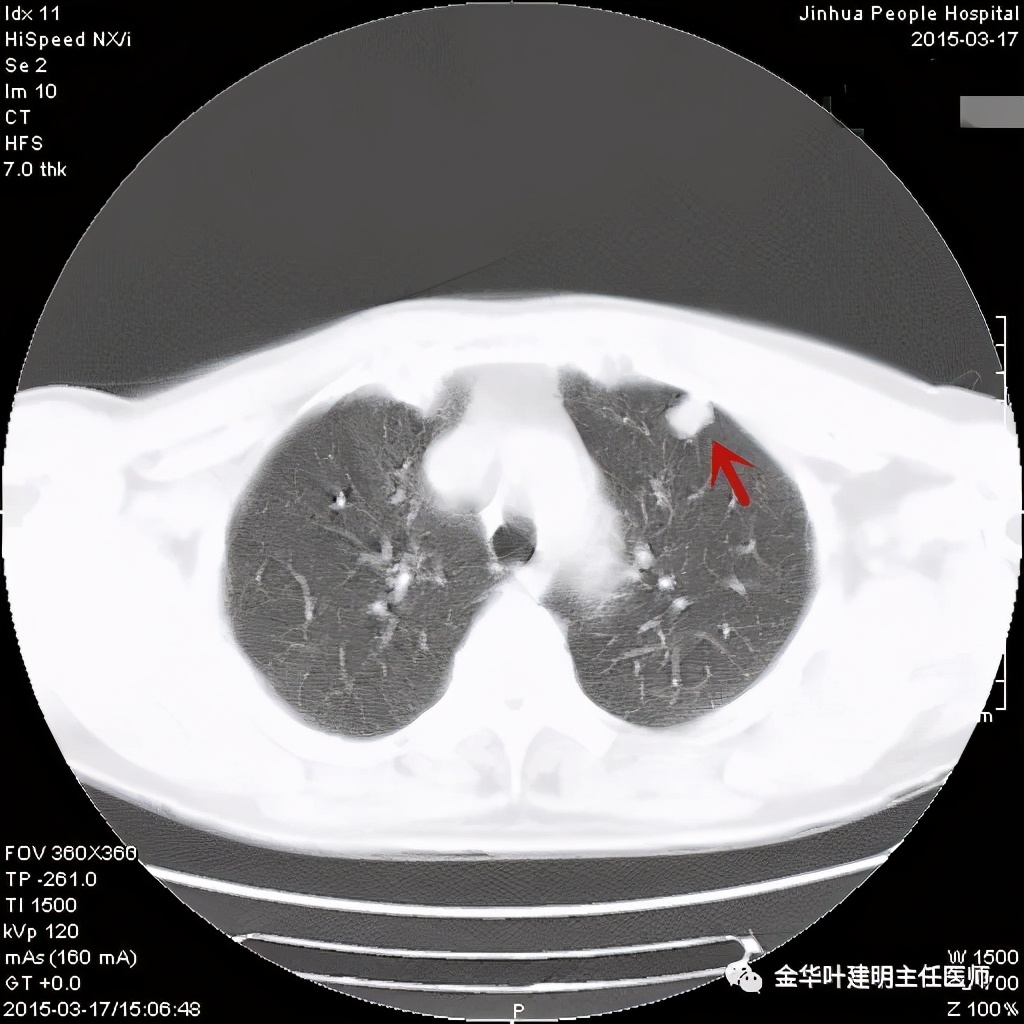

其实今天分享这个病例与我们以往的错构瘤不太一样,以前的影像如下:

亚厘米大小,密度高,周围型,血管贴边

密度高,周围部位,缺乏膨胀性,无收缩力

密度略不均,但边界甚清,边光峭

周围,边缘非常清,病灶内部有点状高密度,约1厘米许,似有微血管征

密度非常高的结节,边缘非常光滑

周围,边缘非常光滑,缺乏收缩力

高密度,周围,边缘非常光滑,亚厘米

高密度,边缘非常光滑,周围

这个也比较大,但边缘非常光滑,密度相对较为均匀

其实我们发现,包括今天这例,只要是错构瘤,“边缘非常光滑”是每一像都具备的!虽然有的似有支气管截断、有的似有血管征、有的似有分叶,但总的只要是边缘非常光滑的实性占位,就要想到错构瘤的可能,若有点状钙化密度,更是强烈要考虑。错构瘤如何靠近胸膜,其实可以切开一点肺实质,挤一下,肿瘤就会滚出来。